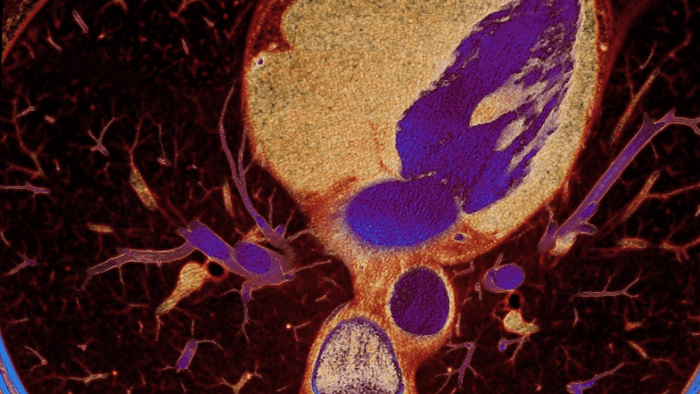

Unlike traditional CT images, spectral-detector CT images capture spectral information 100% of the time —without special planning or set-up. That means you can analyze the spectral data in any image retrospectively, using a variety of spectral viewing tools. You can, for example, adjust the monoenergetic level or get Zeffective maps.

Spectral detector simultaneously absorbs and differentiates high and low energy from a single polyenergetic X-ray beam. Spectral results are acquired within a single scan without the need for special modes.

Detector-based spectral CT simultaneously absorbs high and low energies in the same time and space.